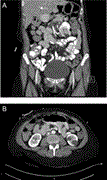

Pancreas graft salvage after successful endovascular treatment of Y graft pseudoaneurysm

V A L Huurman and J H P Lardenoye

Journal of Surgical Case Reports, Volume 2019, Issue 5, May 2019, rjz124, https://doi.org/10.1093/jscr/rjz124